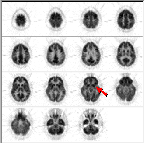

Click on image above to view full-size image.

This is a normal PET scan. Abnormal PET scans will be compared with it in this tutorial about image quality control. The checklist on the right will be completed as we work through image quality control issues relating to neurological scan evaluation. This scan depicts fifteen planes (imaged simultaneously). The top of the brain begins in the upper left corner. Moving from left to right through each row, the final image is from the bottom of the brain.